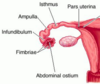

Label all:

Adnexa of uterus =

- ovary + uterine tube